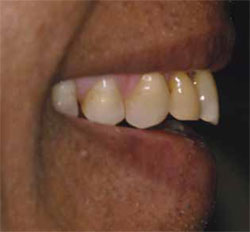

The amount of normal resting maxillary incisal edge display decreases with age due to gravity's effect on the soft tissues.8 With the guidance of photographs, the vertical incisal edge position of the maxillary centrals is planned relative to the upper lip, using standard "E" and rest position views. The trajectory of the incisors and horizontal placement of their incisal edges are equally important, determined relative to the inner vermillion border of the lower lip and the lip closure path using profile smile and tilt-down smile views (Figure 1 and Figure 2). Errors in incisal edge placement can result in problems with phonetics, the neutral zone, and envelope of function. This may also lead to xerostomia and overall patient discomfort.9-11

Figure 1 Profile smile. |  Figure 2 Tilt-down smile.  Figure 3 Full-mouth radiographs. Note location of maxillary sinuses, as well as mesial angulation of teeth Nos. 19 and 32. | |||||